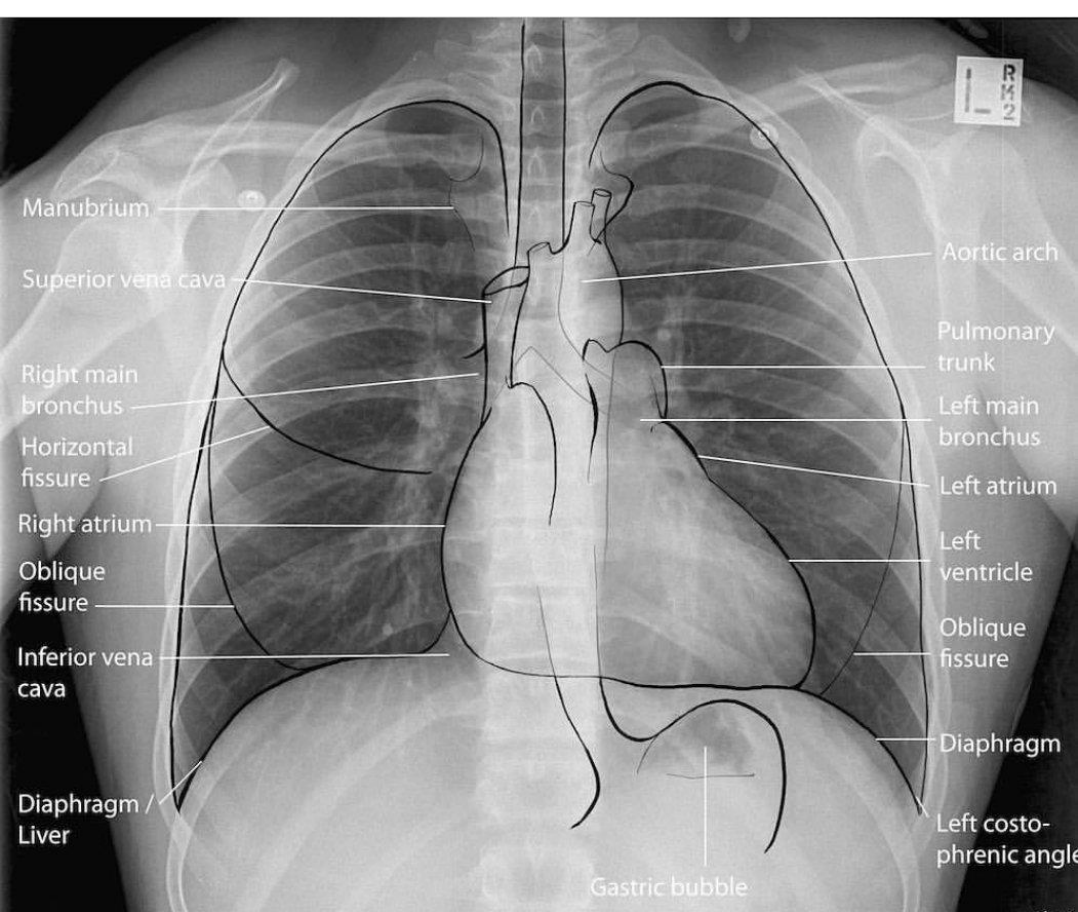

En la radiografía de incidencia de perfil también se ven estructuras mediastinales que están en contacto con parte del

parénquima pulmonar aireado.